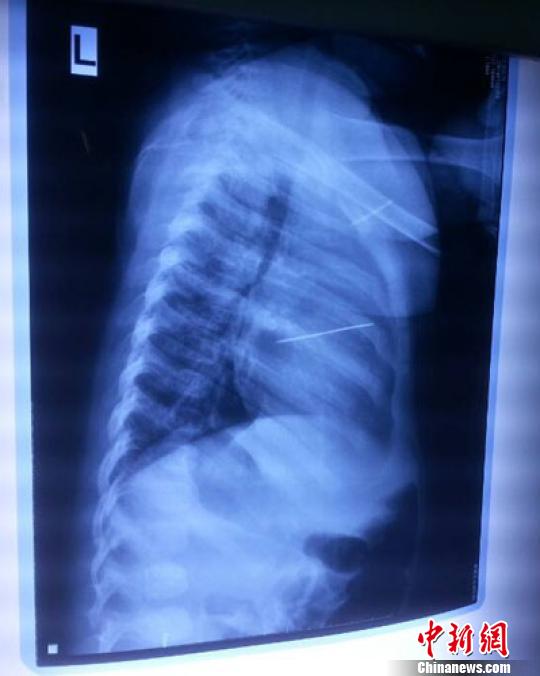

女嬰胸片提示心臟里面扎了一個(gè)縫衣針 蔡迅翔 攝

醫(yī)院胸心外科主任翟波介紹說,1月22日,小患者彤彤因?yàn)榘l(fā)燒抽搐來醫(yī)院就診,常規(guī)檢查時(shí)發(fā)現(xiàn)孩子心臟里面扎了一個(gè)縫衣針。

“第二天上午,我們做了個(gè)緊急彩超檢查,發(fā)現(xiàn)針是從患者右心室表面刺入,穿破室間隔,到達(dá)左心房,中間還有一部分損害到二尖瓣。于23號下午,我們就做了一個(gè)緊急手術(shù),手術(shù)中發(fā)現(xiàn),這枚針已經(jīng)刺入心臟,沒入了右心室的下面,表面已經(jīng)看不到針了,僅能看到一個(gè)小針眼,還在往外滲血,一點(diǎn)一點(diǎn)的滲,心包腔里面大概有100多毫升的出血,心包上一個(gè)洞,針在右心室表面刺入以后,穿過室間隔,在二尖瓣的上方,進(jìn)入了左心房,在針的四周,有很多纖維沉積物,包繞著這枚針?!钡圆ㄕf,他們把針取出來以后,測量了一下,長度大概是五厘米,同時(shí)發(fā)現(xiàn)這個(gè)針給患者左心房的后壁造成了一定的損傷,左心房的后壁已經(jīng)損傷了三分之二,還剩下有左心房的外膜,很薄的一層,如果這一層再破的話,這個(gè)孩子將會(huì)引起大出血,很快就會(huì)死亡。